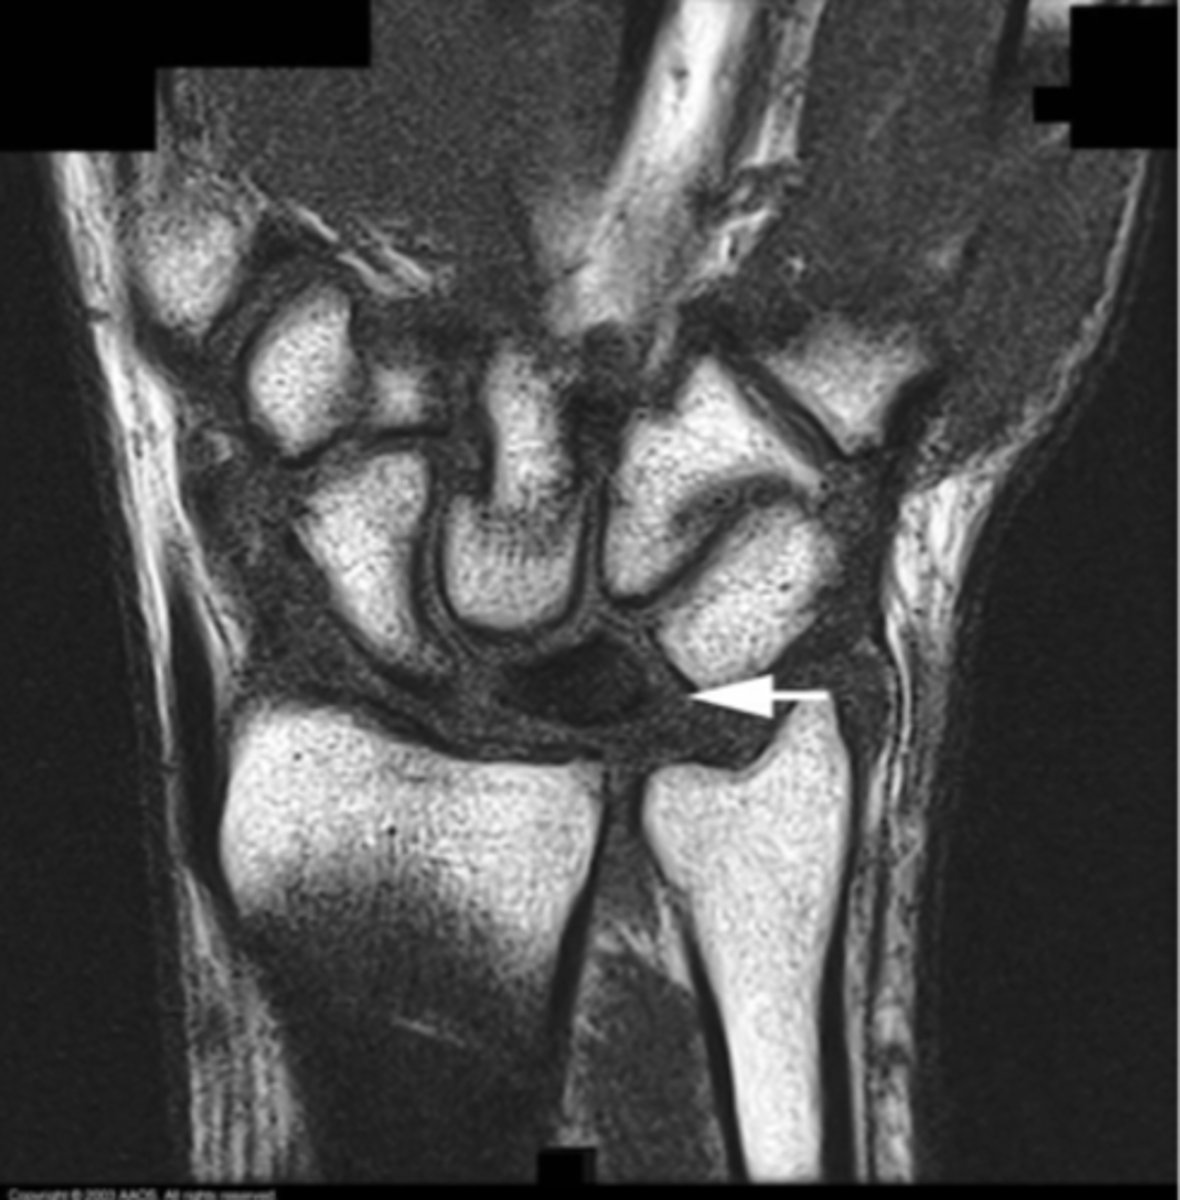

Ganglion cyst

What is the issue?